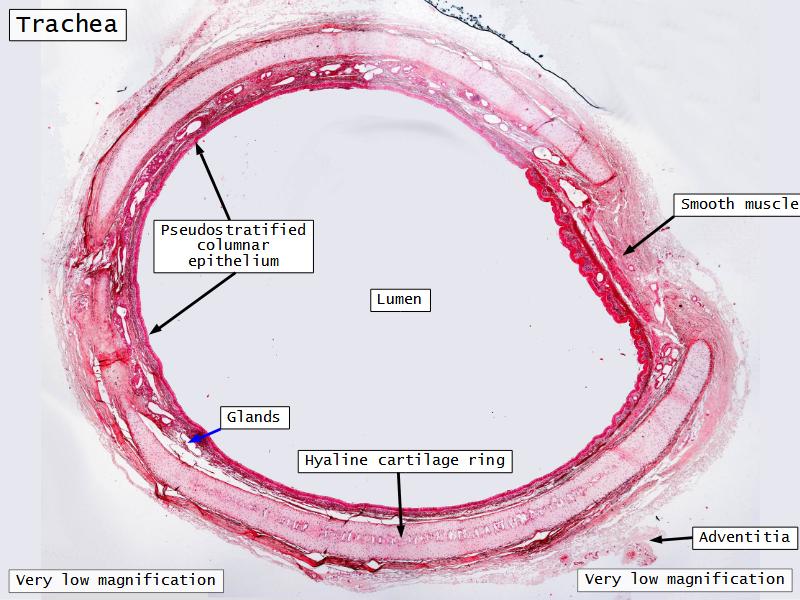

Trachea

Bronchi - Transitions

- Intrapulmonary bronchi

- Irregular cartilage

- Respiratory epithelium

- Glands